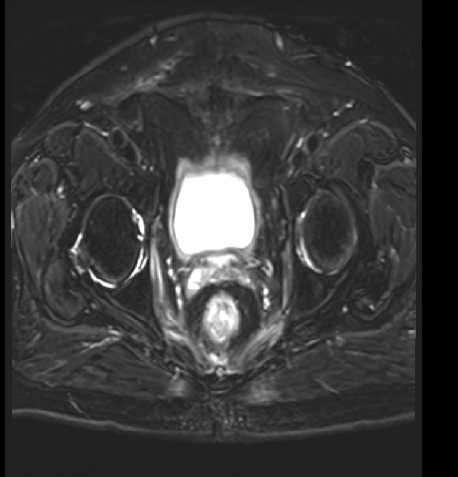

MR:1、直肠癌(T3可能),与右侧肛提肌关系密切,考虑1、炎性渗出粘连2、侵犯待排2、慢性膀胱炎3、前列腺增生。

2017-09 MR:

2018年11月:直肠壁异常信号,考虑复发

2019-06:

2020-05:

2019-06:

2020-05: